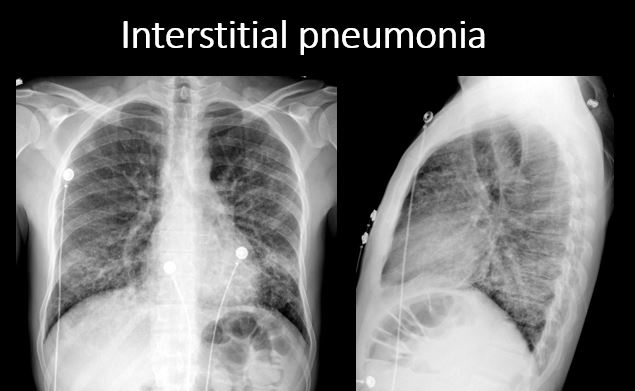

There is focal or diffuse interstitial disease. |

No | NA |